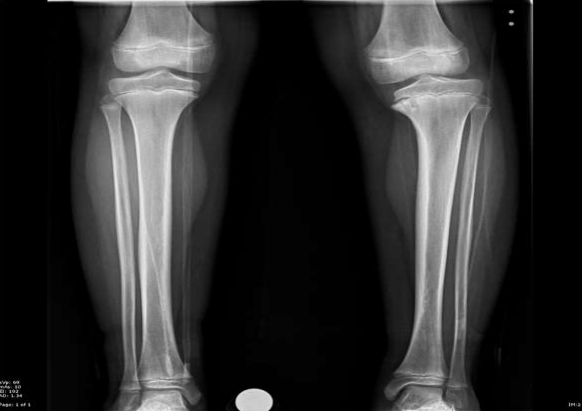

• Tibial varum (Blount) in juveniles: Pathological genu varum in children over 10 years of age. Tibial varus in infants is more unilateral, usually bilateral (Figure 8). Osteogenesis imperfecta, various exostoses, Maffucci syndrome, Ollier disease, congenital pseudoarthrosis (anterolateral curvature) of the tibia.

Figure 8: Adolescent tibia vara